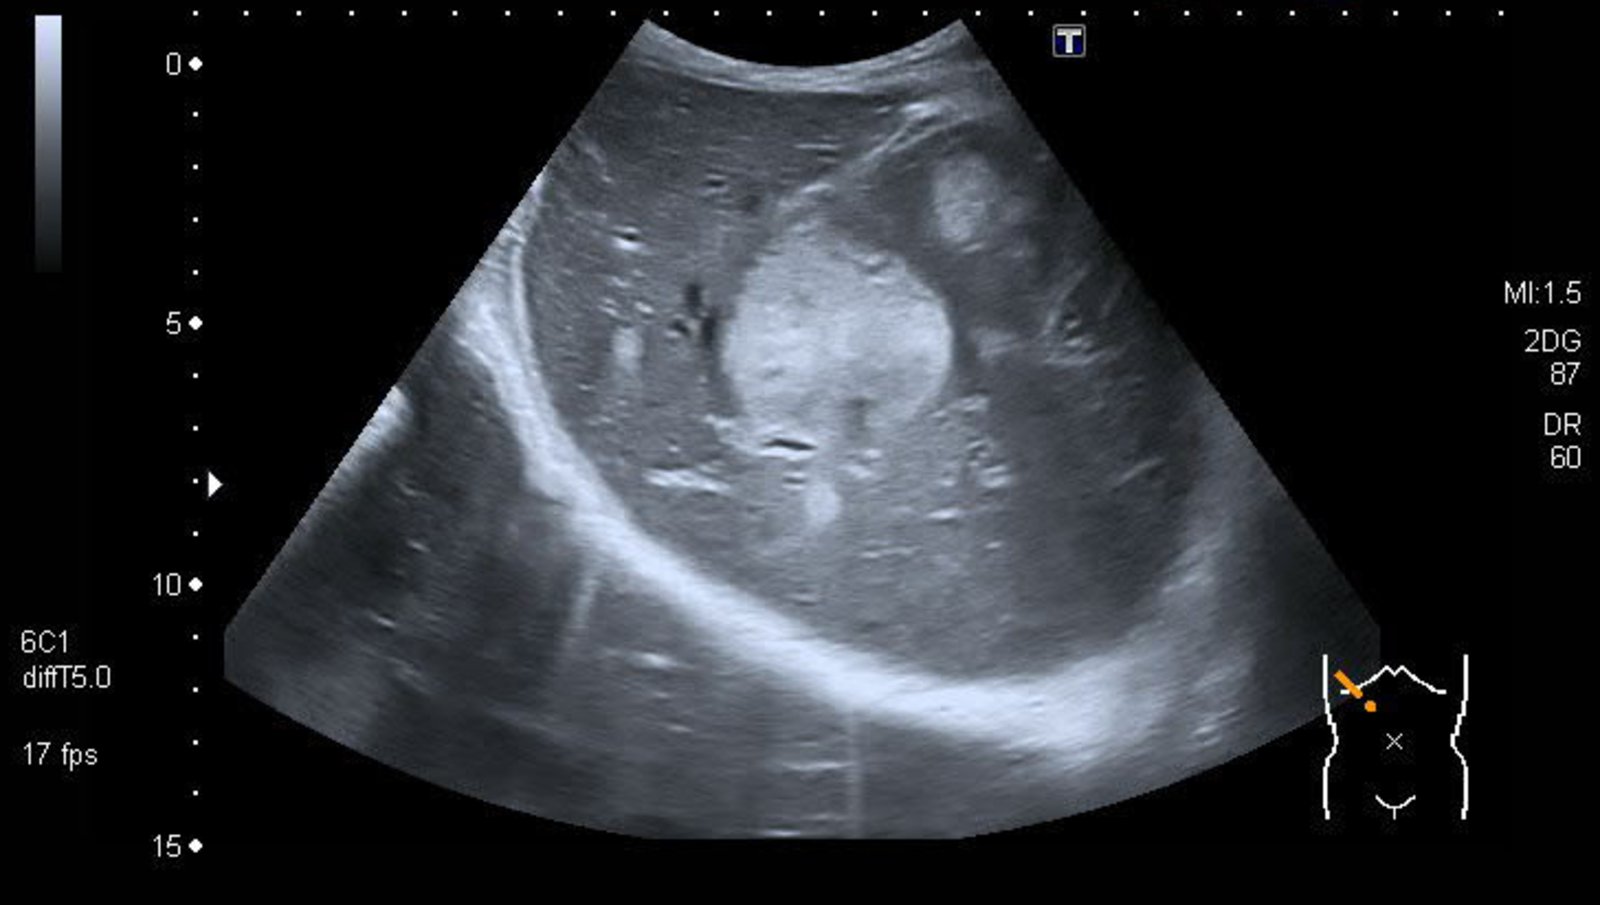

Imaging [1][7]

Imaging studies are used to locate primary and metastatic NENs.

• Abdominal imaging, e.g., CT, MRI, or ultrasound